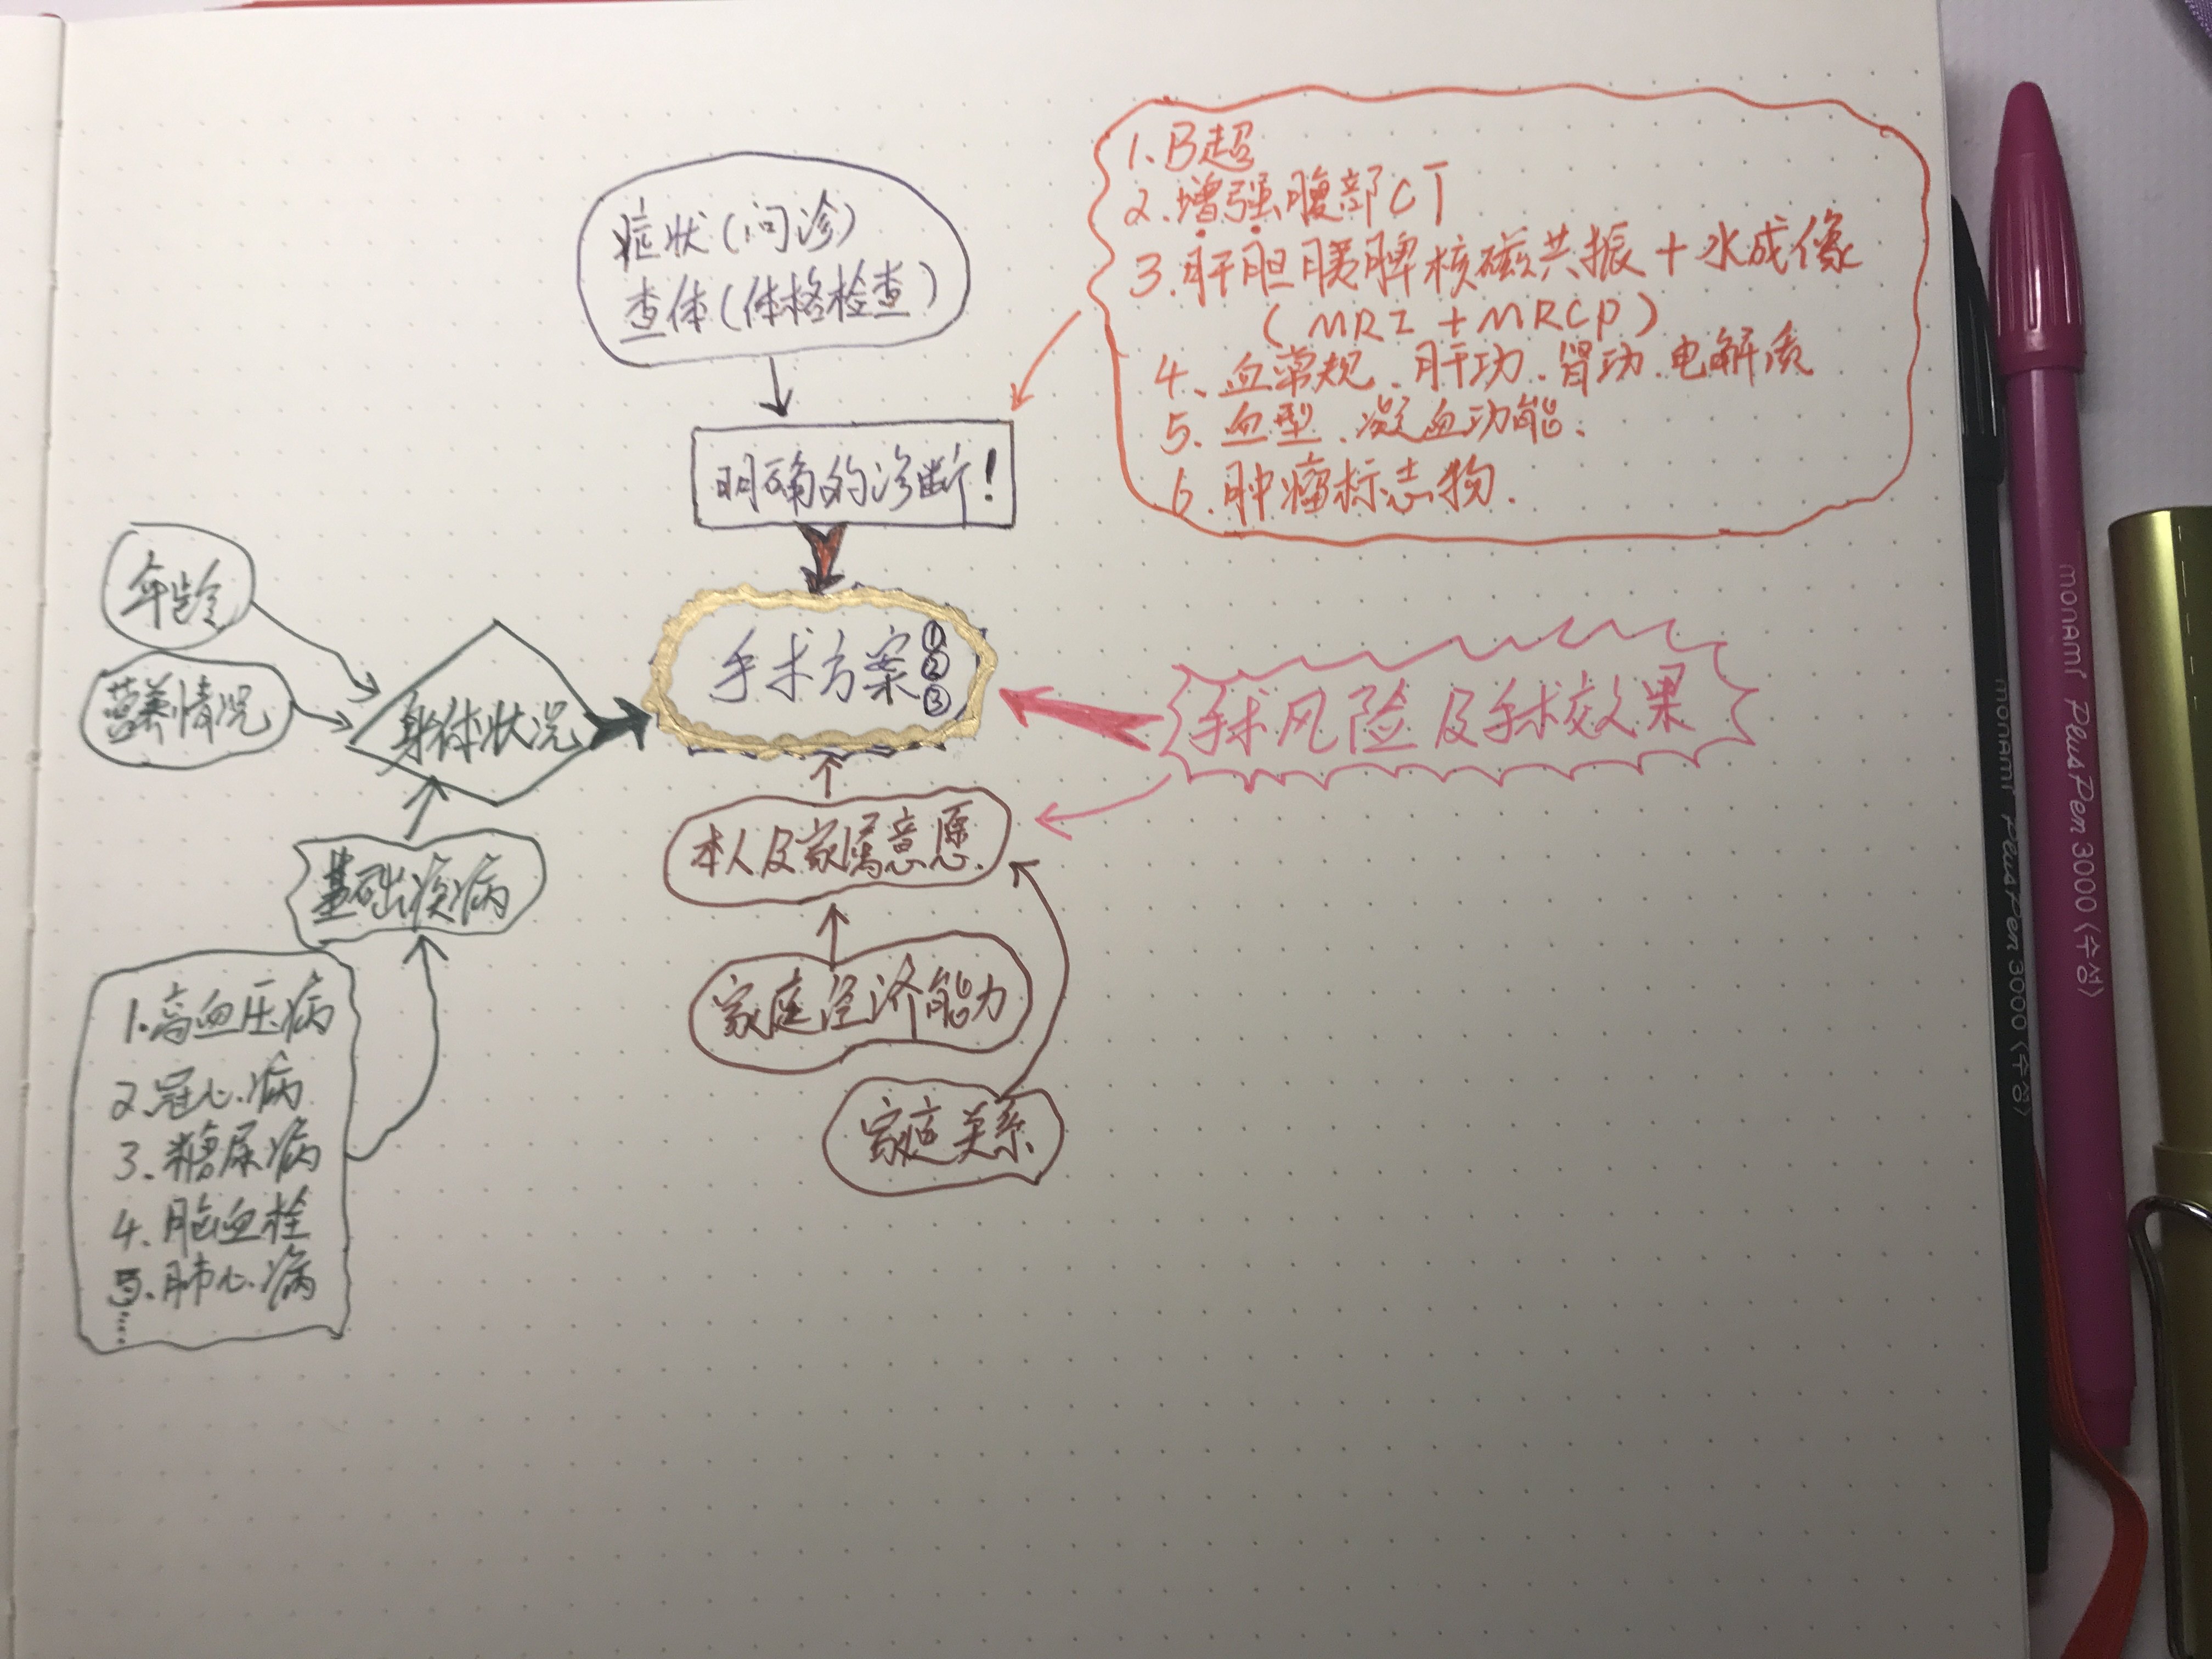

但你知道要有准确的诊断是需要多项检查来确定,确定诊断后会有多种不同的手术方案,而且需要根据患者的身体情况、手术的效果及风险、本人和家属的意愿以及经济能力来决定的。

为什么要尽量完善的上传检查片子及报告?

②我们专科医师看片子需要根据专科的角度去判断片子中疾患的部位、大小、血液供应、周围粘连、目前疾患的进展、甚至手术方案、病情的预后都已经了然在心中了。

如何正确的把拍的片子发给医生看!

一般的报告就不再说了,正常拍摄就可以,我说的是片子应该怎么拍,一般是1-4小张拍一次,如下图: